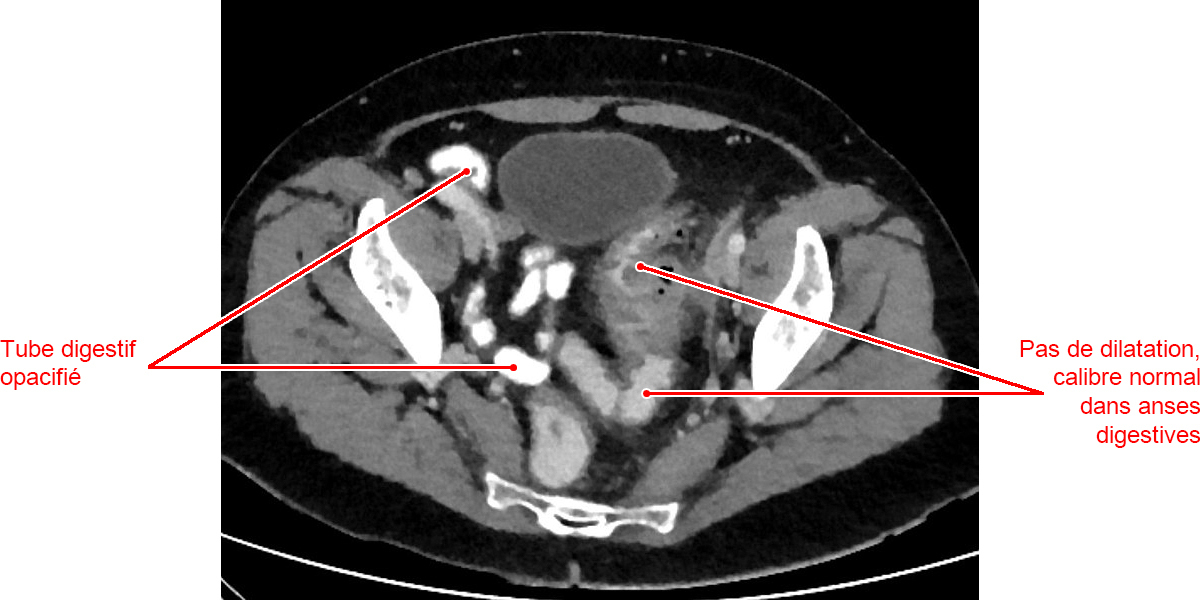

Hellerhoff, 7 novembre 2020. On note sur le scanner abdominopelvien la présence de plusieurs diverticules (petites bulles d’air au sein de la paroi colique) ; un épaississement de la paroi colique ; une infiltration de la graisse péridiverticulaire.